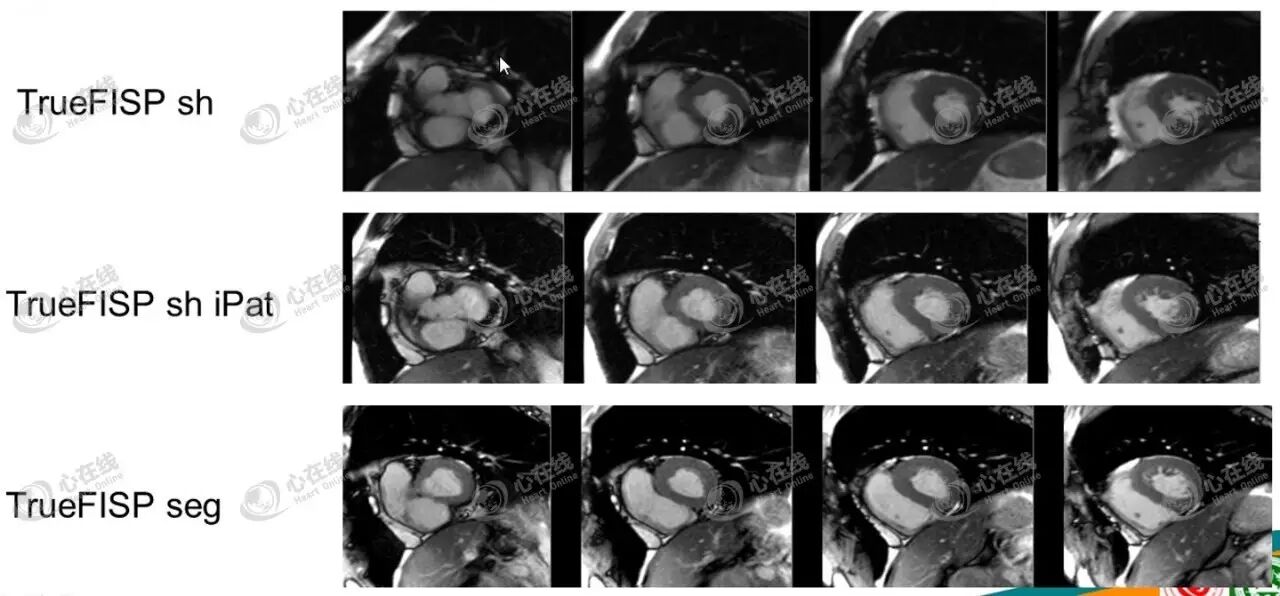

2)亮血序列。图2为不同采集方法获得的TrueFISP亮血序列图像。

图2